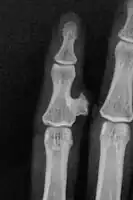

Medical imaging usually shows a well-defined wide-based bony growth on the surface of bone.[5] It can be pedunculated and irregular, giving it a "bizarre" appearance, and is not connected to underlying bone.[2]

X-ray hand, BPOP 2nd metacarpal

X-ray hand, BPOP 2nd metacarpal (side view)